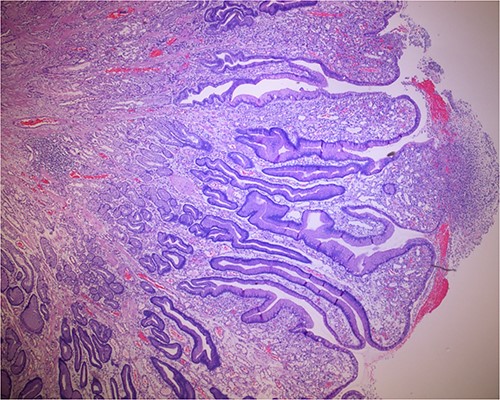

Histologic sections of the polyps demonstrated benign gastric hyperplastic polyps with acute and chronic gastritis (Fig. 2). Portions of the gastric polyps and adjacent mucosa were covered by inflammatory cell exudate (Fig. 3). Higher magnification revealed conspicuous volcanic-like eruption of the exudate, reminiscent of pseudomembranous gastritis (Fig. 4). Alcian yellow and GMS stains were negative for Helicobacter pylori and fungal organisms, respectively.

Biopsy of the gastric polyps is consistent with hyperplastic polyps, focally covered by inflammatory volcanic eruption.

Biopsy of the polyp, covered in part by pseudomembranous inflammatory exudate.